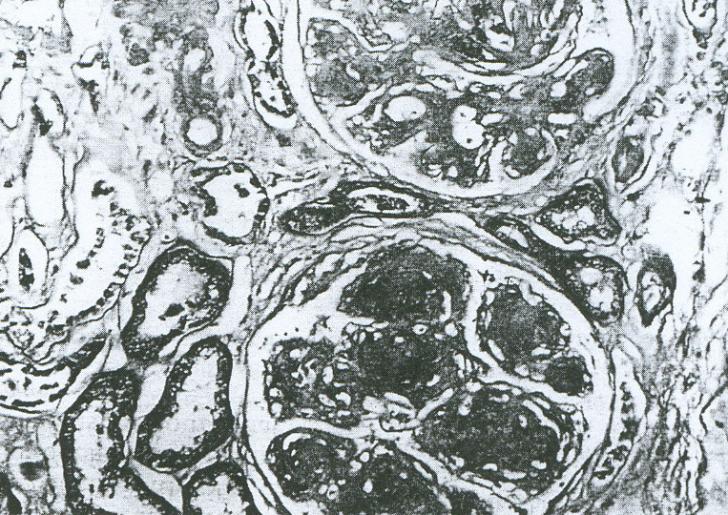

Glomerulopatii ereditare

Glomerulopatii ereditare Sindromul nefrotic congenital Sindromul nefrotic congenital este prezent inca din primele trei luni de viata, fiind asociat cu o serie de circumstante, majoritatea fiind boli familiale. Cele mai multe din aceste aCiteste tot ... 1121 cuvinte

Dimensiune mica

+ cu imagini |